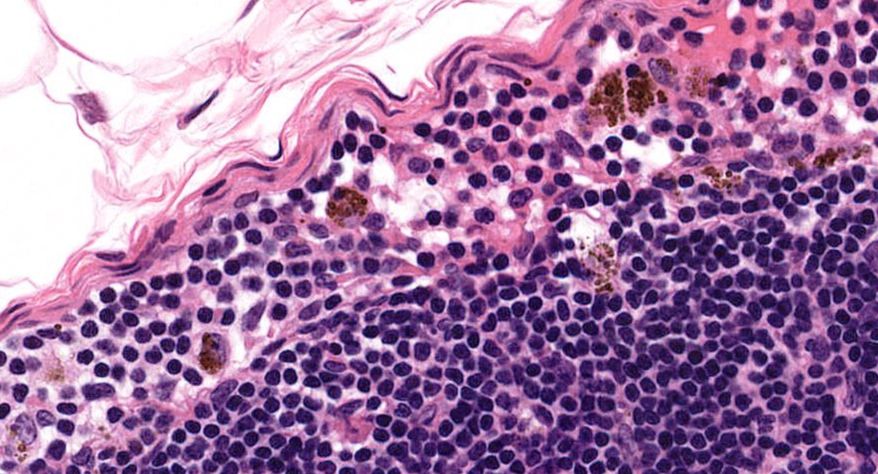

低倍镜:胸腺表面包有薄层结缔组织构成的被膜,结缔组织深入实质,将胸腺分成许多不完整的小叶。每个小叶分为周围的皮质和中央的髓质两部分。皮质中胸腺细胞排列密集,故染色深;髓质中胸腺细胞较少,胸腺上皮细胞多,故染色浅,其中可见染成红色的圆形小体-胸腺小体。高倍镜:胸腺小体大小不等,由几层至十几层扁平的胸腺上皮细胞呈同心圆状排列而成,其外周的细胞较幼稚,细胞核明显;小体中央部分的上皮细胞已退化,细胞核消失,胞质呈均质状,染成红色。

1.成人胸腺全景图

2.被膜

3.皮质